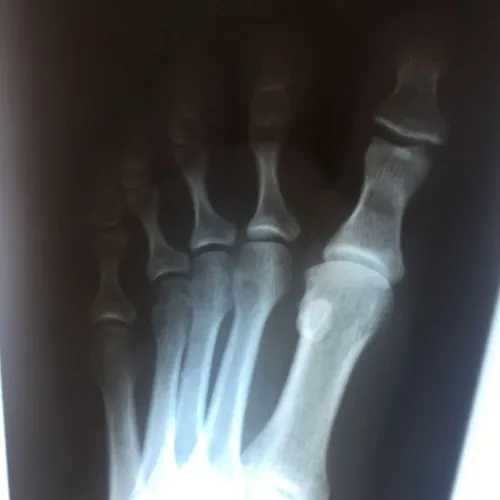

Patient had chronic pain after comminuted sesamoid fracture. After conservative care, patient had total sesamoidectomy and is pain free 3 months postop

Pre and Postop Tibial Sesamoidectomy